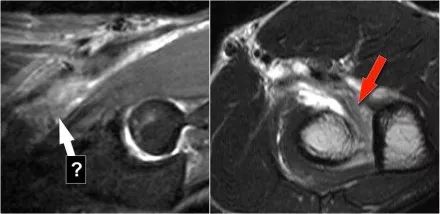

下面这是另一个例子。在T1W图像上有一些增厚和一些中间信号。这可能是肌腱变性,但总是看T2W图像寻找撕裂。在这种情况下,有部分撕裂。

下面是另一种情况。在矢状图像上,我们不确定可能的撕裂。也许只有一些肌腱炎或肌腱炎。轴向图像显示部分撕裂(红色箭头)。

始终确保你的轴向扫描一直到结节,因为你太早停止,就像在这种情况下,你只会看到增厚的肌腱和一些液体,但你不确定可能的撕裂。